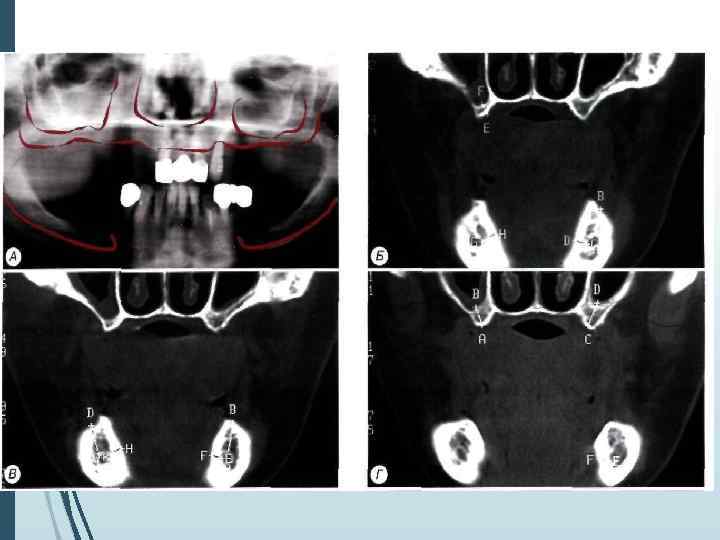

Однако следует учитывать, что даже при правильной укладке и методике ортопантомография даёт искажения реальных размеров челюстей до 10% по вертикали и до 20% по горизонтали. При неправильном положении пациента во время обследования или нарушении режима работы ортопантомографа искажения (увеличение размеров) могут достигать 32% по вертикали и 50 -70% по горизонтали

Компьютерная томография является одним из наиболее информативных методов рентгенологического обследования. С высокой степенью достоверности она позволяет определить высоту и ширину кости, топографию нижнечелюстных каналов и верхнечелюстных пазух, особенности архитектоники различных отделов челюстей, соотношение последних, а также создать трёхмерное изображение лицевого отдела черепа